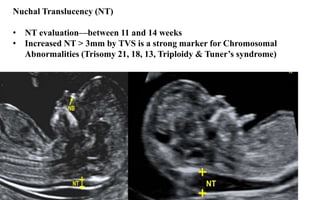

Nuchal Translucency (NT)

• NT evaluation—between 11 and 14 weeks

• Increased NT > 3mm by TVS is a strong marker for Chromosomal

Abnormalities (Trisomy 21, 18, 13, Triploidy & Tuner’s syndrome)

Nuchal Translucency (NT) •NT evaluation—between 11 and 14 weeks • Increased NT > 3mm by TVS is a strong marker for Chromosomal Abnormalities (Trisomy 21, 18, 13, Triploidy & Tuner’s syndrome)